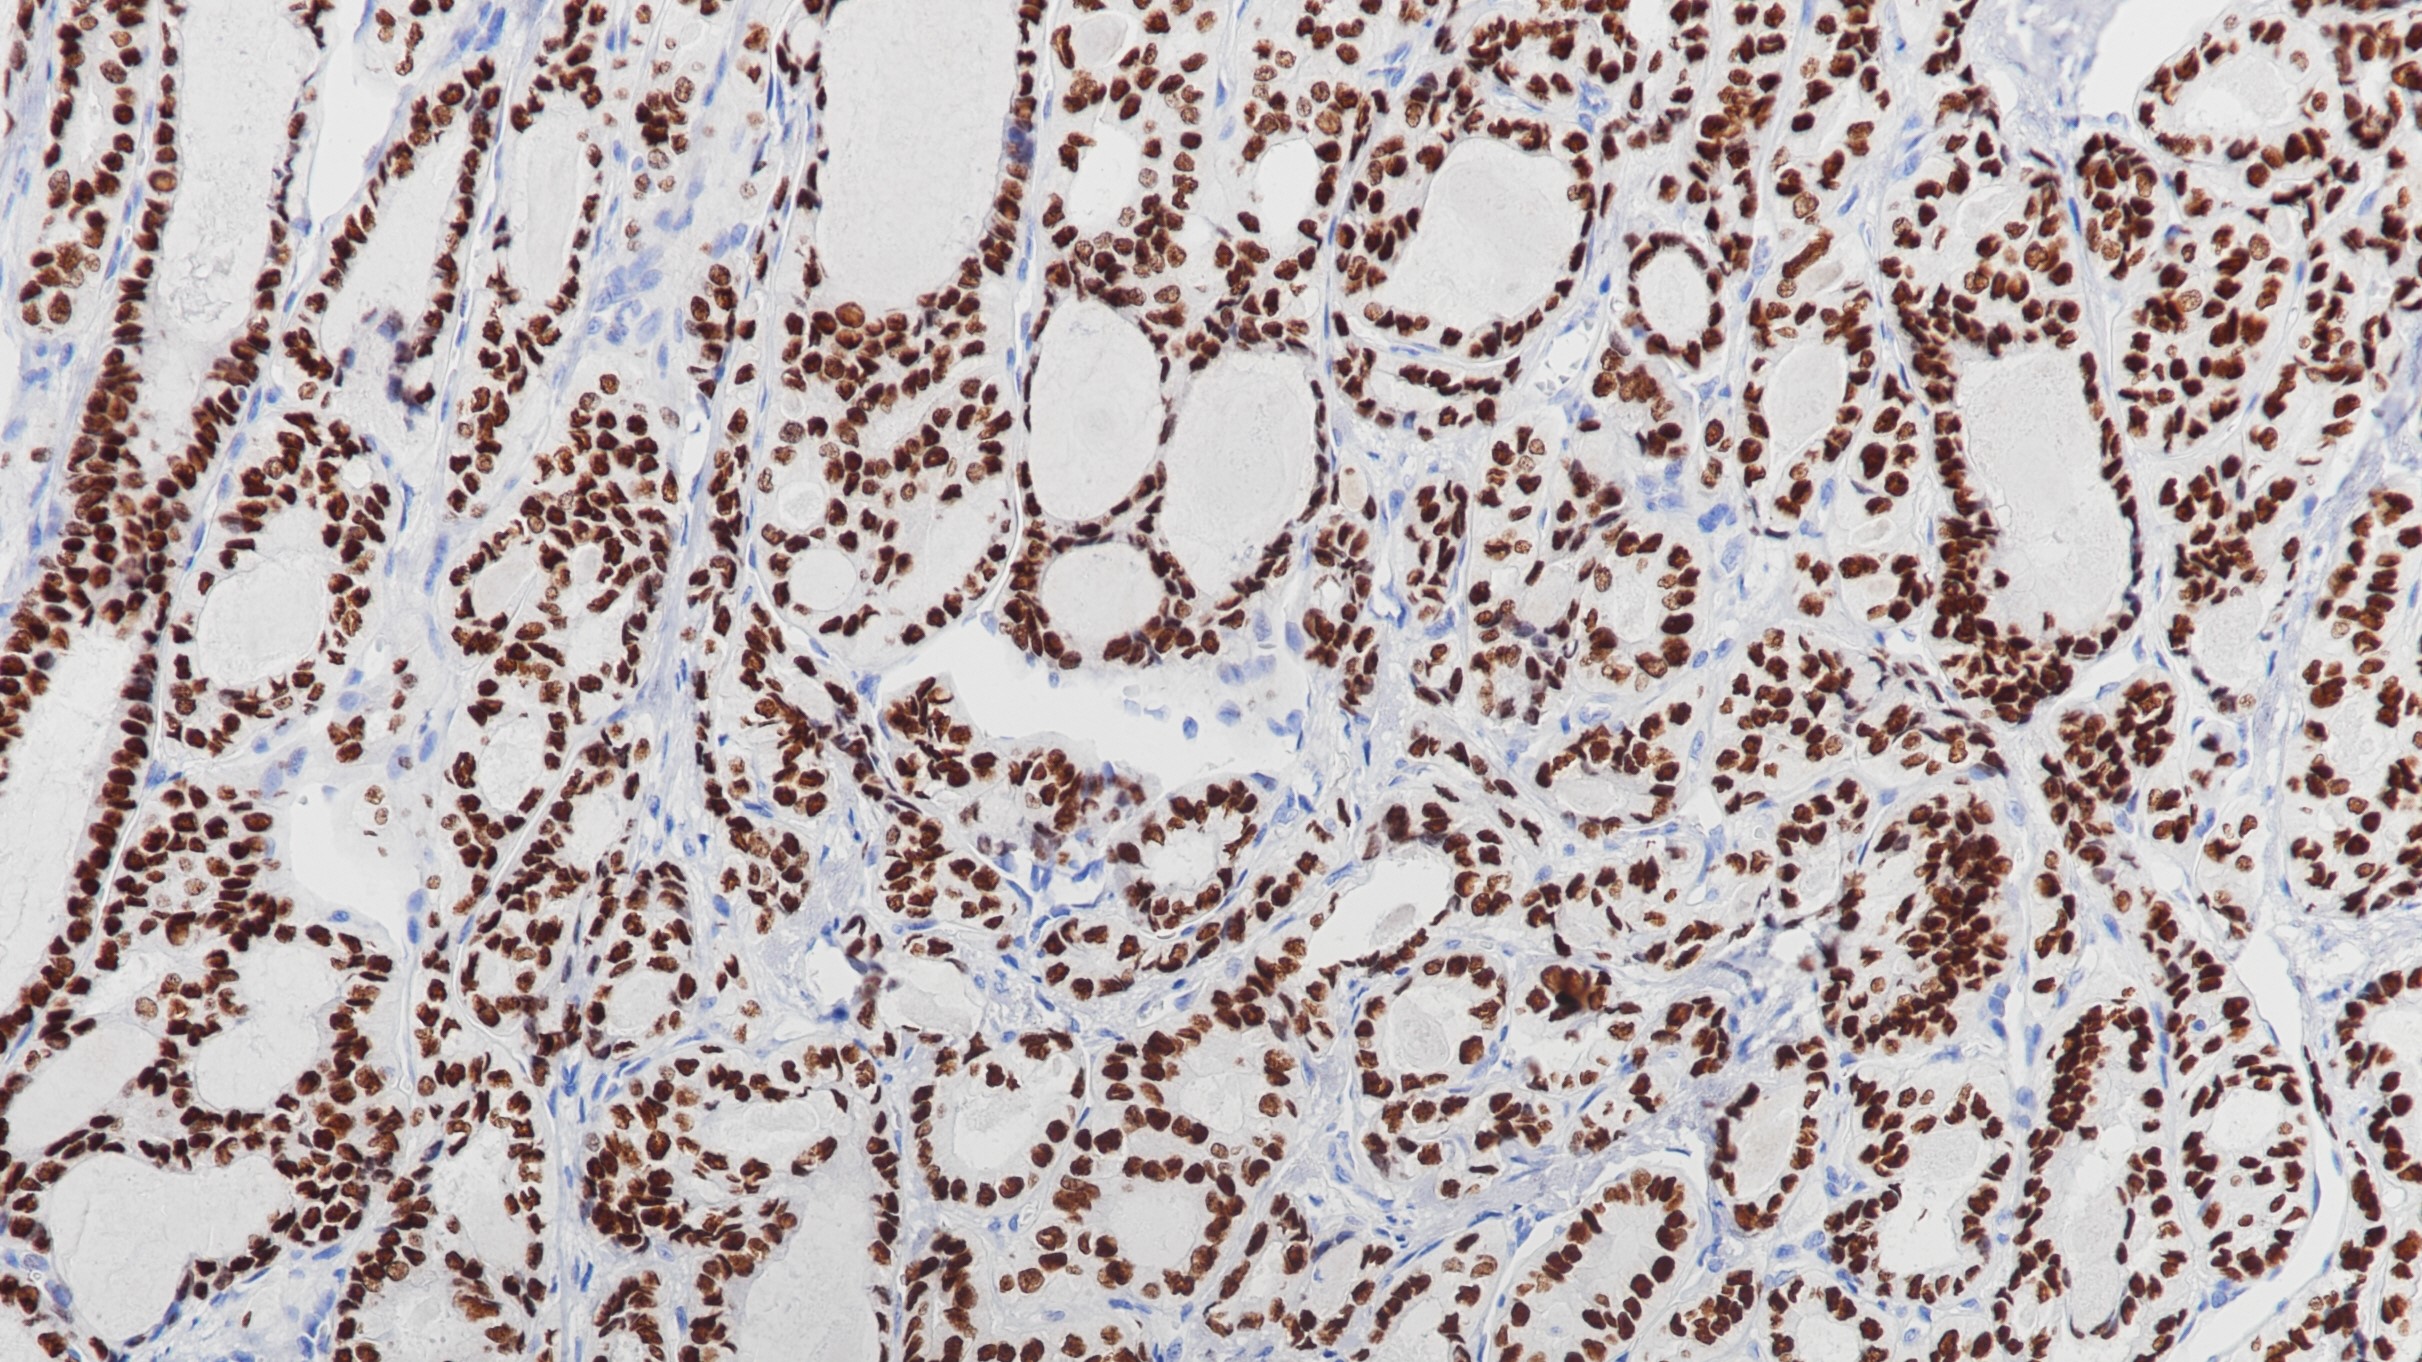

1. Loreto C D , Puglisi F , Lauro V D , et al. TTF-1 protein expression in pleural malignant mesotheliomas and adenocarcinomas of the lung[J]. Cancer Letters, 1998, 124(1):0-78.

2. Wu M ,Szporn A H , Zhang D , et al. Cytology applications of p63 and TTF-1 immunostaining in differential diagnosis of lung cancers[J]. Diagnostic Cytopathology, 2005, 33(4):223-227.